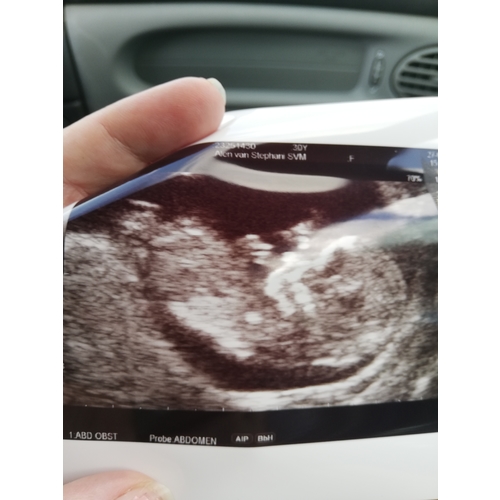

Afgaand op de NUB theorie is mijne een meisje denk ik?

11+2 en de verloskundige zei dat ze het zag maar volgensmij is het echt te vroeg

Lieve mensen, elke baby is in het begin een meisje vanuit daar groeit de clitoris naar een piemeltje, of het blijft. Echt wachten tot zeker 16 weken....

Ahh oké. De nub kun je eigenlijk pas met 12 weken echt inschatten. De verlo ...

Ze zei een meisje